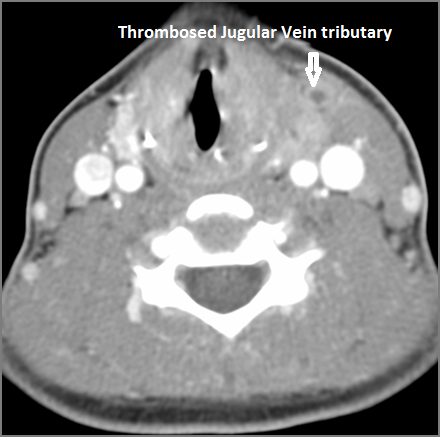

Vascular Findings

There is evidence of thrombus,thrombophlebitis or other occlusive or inflammatory process of the jugular vein or smaller venous tributaries.

There is evidence of thrombus, thrombophlebitis or other occlusive or inflammatory processsmaller jugular venous tributaries.